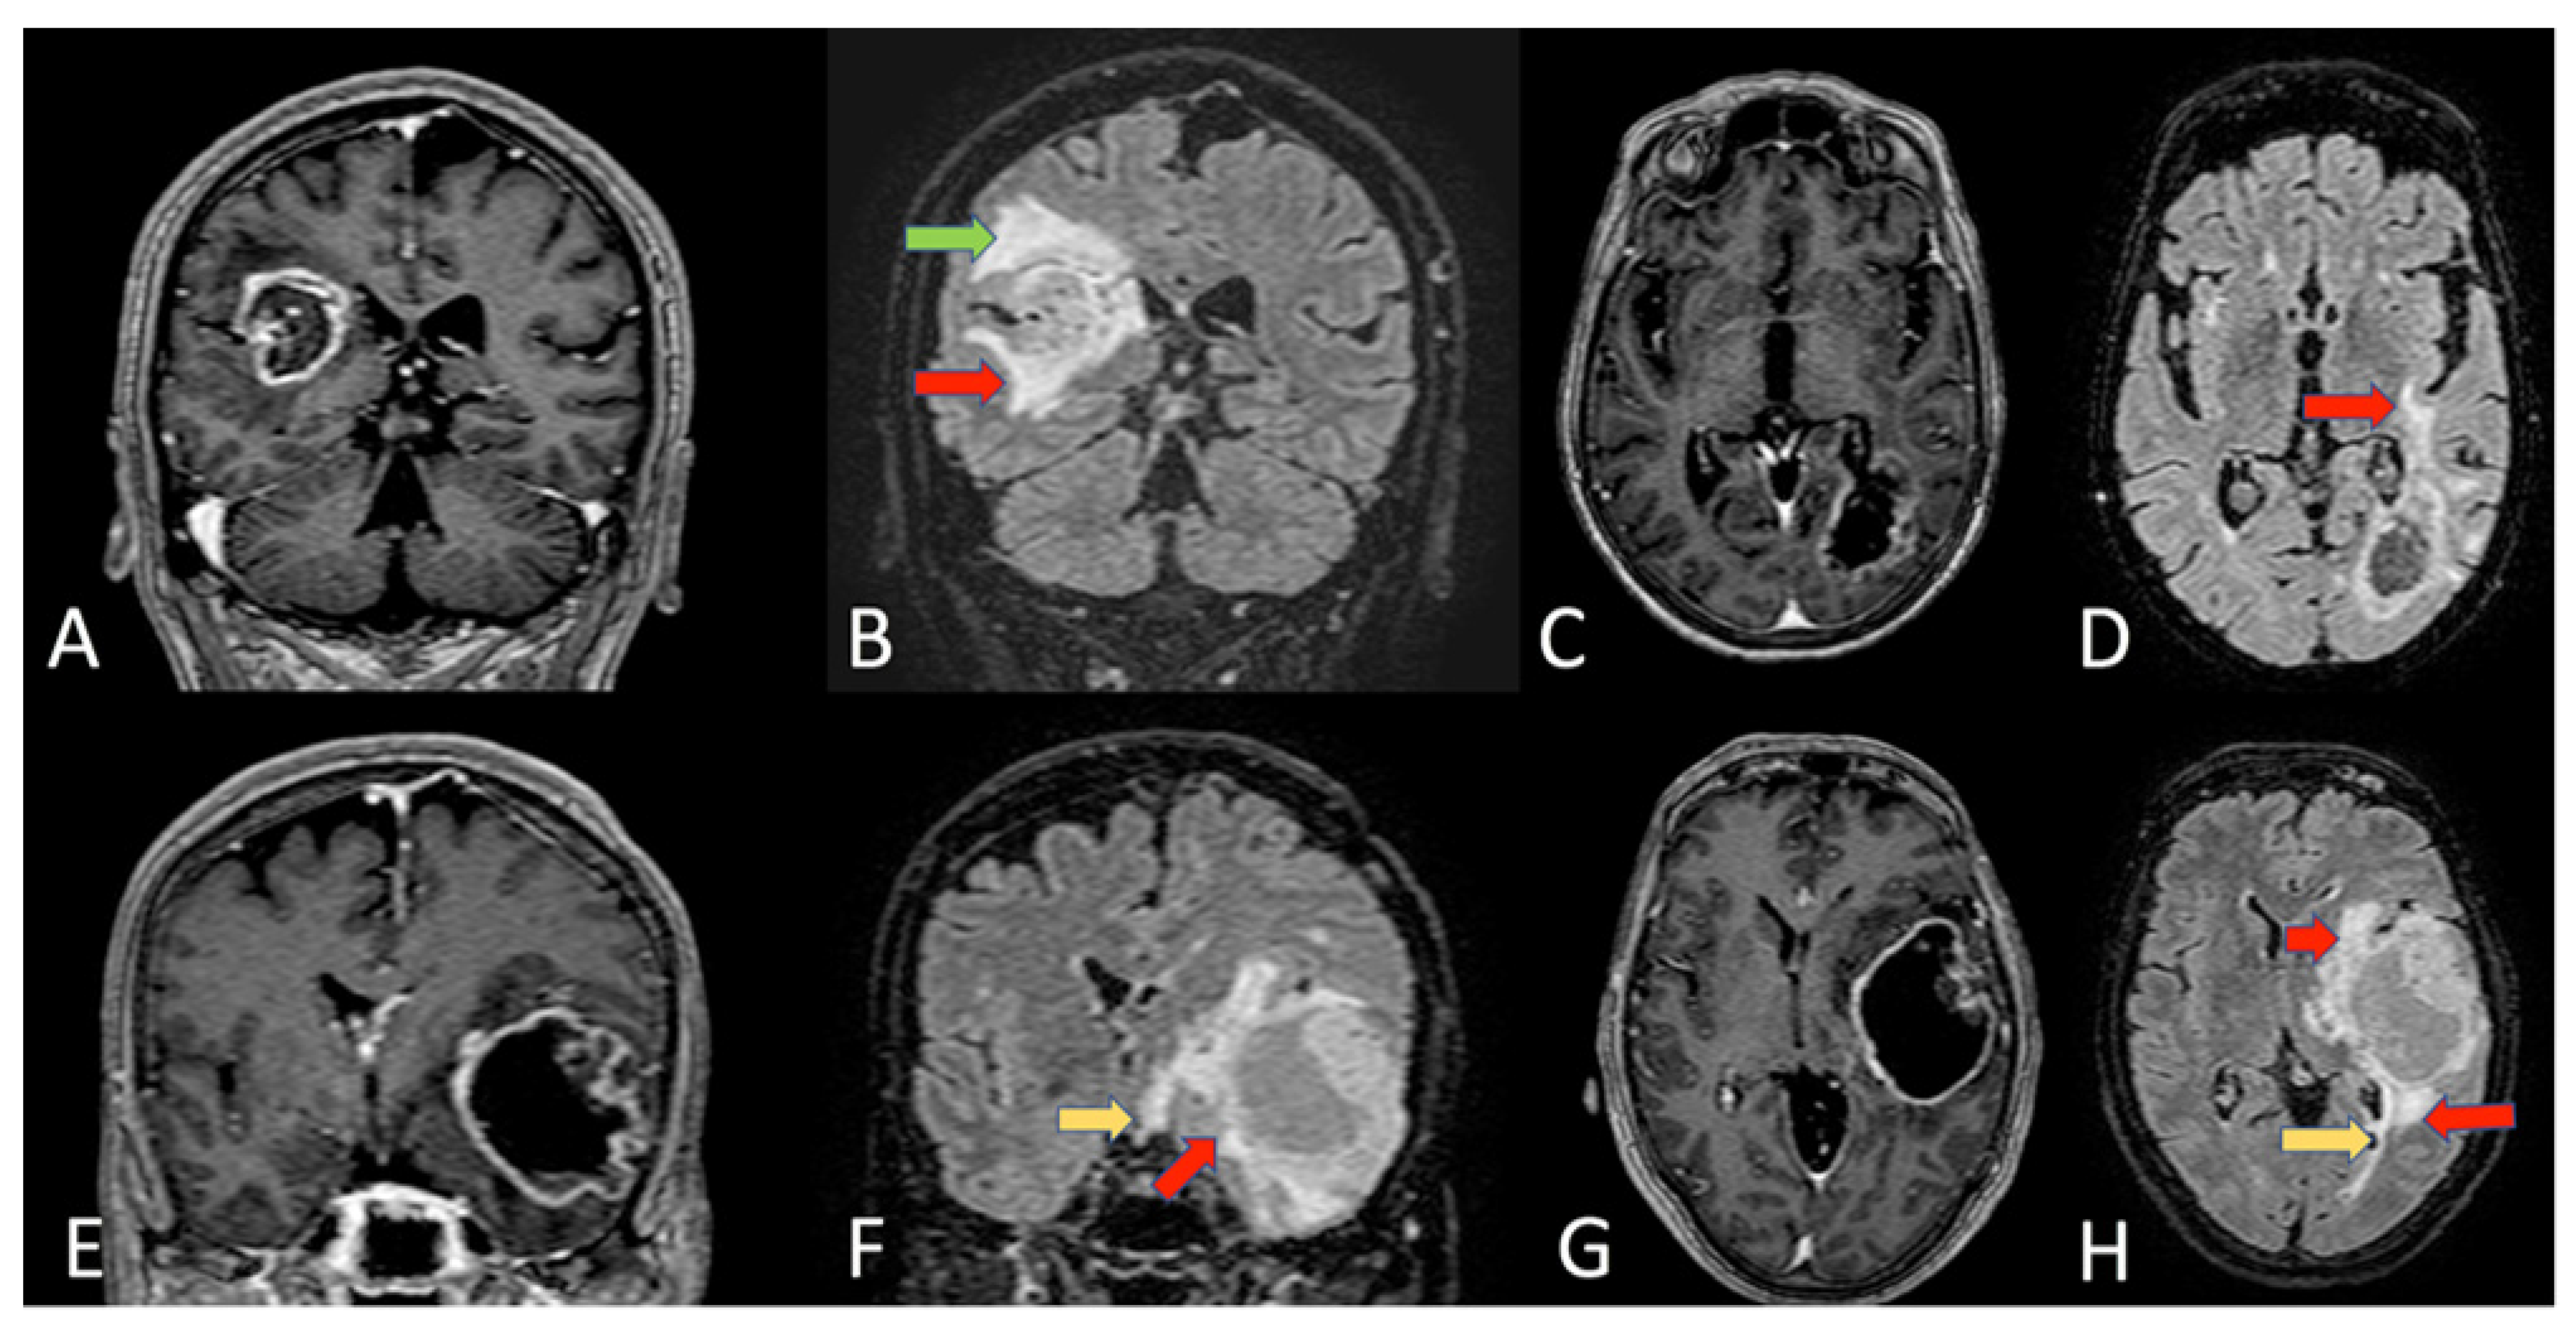

- Altieri, R.; Barbagallo, D.; Certo, F.; Broggi, G.; Ragusa, M.; Di Pietro, C.; Caltabiano, R.; Magro, G.; Peschillo, S.; Purrello, M.; et al. Peritumoral Microenvironment in High-Grade Gliomas: From FLAIRectomy to Microglia-Glioma Cross-Talk. Brain Sci. 2021, 11, 200. [Google Scholar] [CrossRef]

- Altieri, R.; Melcarne, A.; Junemann, C.; Zeppa, P.; Zenga, F.; Garbossa, D.; Certo, F.; Barbagallo, G. Inferior Fronto-Occipital fascicle anatomy in brain tumor surgeries: From anatomy lab to surgical theater. J. Clin. Neurosci. 2019, 68, 290–294. [Google Scholar] [CrossRef] [PubMed]

- Altieri, R.; Raimondo, S.; Tiddia, C.; Sammarco, D.; Cofano, F.; Zeppa, P.; Monticelli, M.; Melcarne, A.; Junemann, C.; Zenga, F.; et al. Glioma surgery: From preservation of motor skills to conservation of cognitive functions. J. Clin. Neurosci. 2019, 70, 55–60. [Google Scholar] [CrossRef] [PubMed]